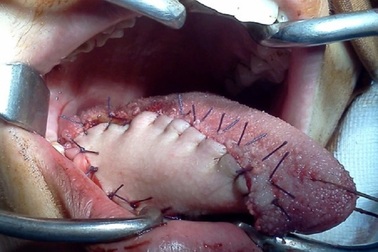

Tái tạo lưỡi bằng vạt da cho bệnh nhân ung thưBị ung thư lưỡi chuyển sang giai đoạn di căn hạch vùng cổ, bác sĩ buộc phải cắt bỏ nửa lưỡi bên trái của bệnh nhân Đ.T. Bằng kỹ thuật vi phẫu mạch máu và thần kinh, phần lưỡi bị cắt được tái tạo từ vùng vạt tự do mặt trước cẳng tay bệnh nhân.

Phương pháp mới tái tạo lưỡi cho bệnh nhân ung thưBằng phương pháp sử dụng vạt cơ dưới móng, các bác sĩ tại bệnh viện Chợ Rẫy đã tái tạo thành công lưỡi và sàn miệng bị cắt do ung thư cho 7 bệnh nhân. Phương pháp trên mở ra một hướng mới giúp bệnh nhân giữ được chức năng của lưỡi và sàn miệng.

Thích hút thuốc, người phụ nữ trẻ phải cắt lưỡi vì ung thưĐể tái tạo lại chiếc lưỡi bị cắt bỏ, các bác sĩ đã dùng một mảng da, cơ và gân ở cánh tay của cô. Theo chia sẻ của nhân vật chính, quá trình lột da ở tay thậm chí còn còn đau hơn cả phẫu thuật trên lưỡi.